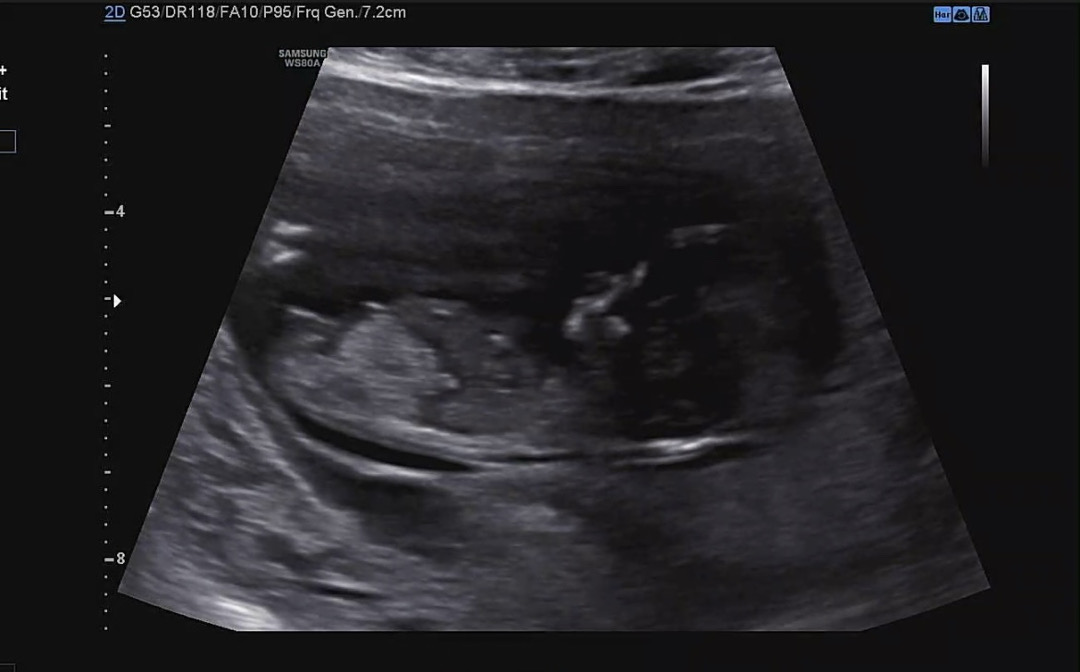

11주 6일 각도법 봐주세요💗

11주 6일 초음파에요! 제가 다니는 병원은 20주차에 알려준다고 해서 넘 궁금하네요😭